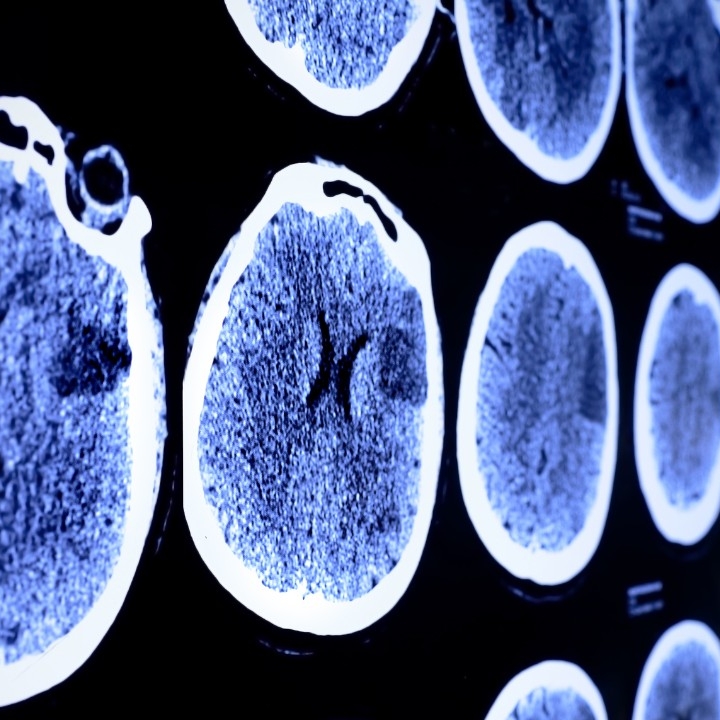

What has the brain cancer spore at md anderson cancer center accomplished? This technology images the brain during surgery, helping neurosurgeons safely remove as much of the tumor as possible. Some inherited disorders linked to brain cancer include.

Among these technologies is the brainsuite® intraoperative mri, found in just a handful of hospitals around country. At md anderson’s brain and spine center, these surgeons have access to the most advanced surgical technologies in the world. These topic labels come from the works of this organization�s members.